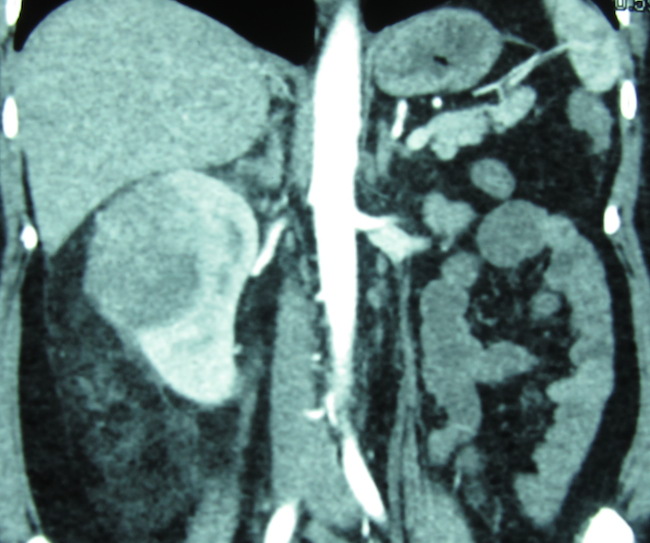

злокачественная шванома